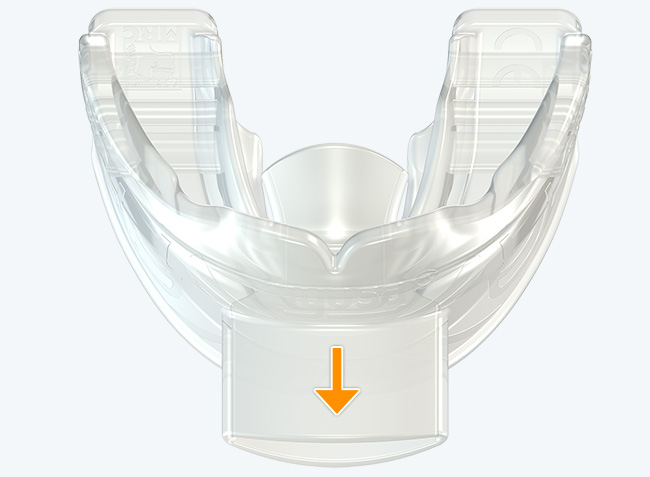

Myosa® for TMJBDS® Stage 1 Hybrid - S1H

Establish a functional airway and permits active exercises

The Myosa® for TMJBDS® S1H is specifically designed for patients who are breathing and disordered sleep (BDS) primary with moderate to severe BDS as indicated by a Breath Hold Time (BHT) of 20 or less. These patients may or may not have TMJ disorders, but due to the severity of their BDS, they require immediate improvement of their airway. The features of the appliance not only work to open the airway, but also allow patients to undertake initial exercising of the lip, tongue and airway muscles. Progress to the S1 when the patient’s BHT reaches 20 seconds or more.